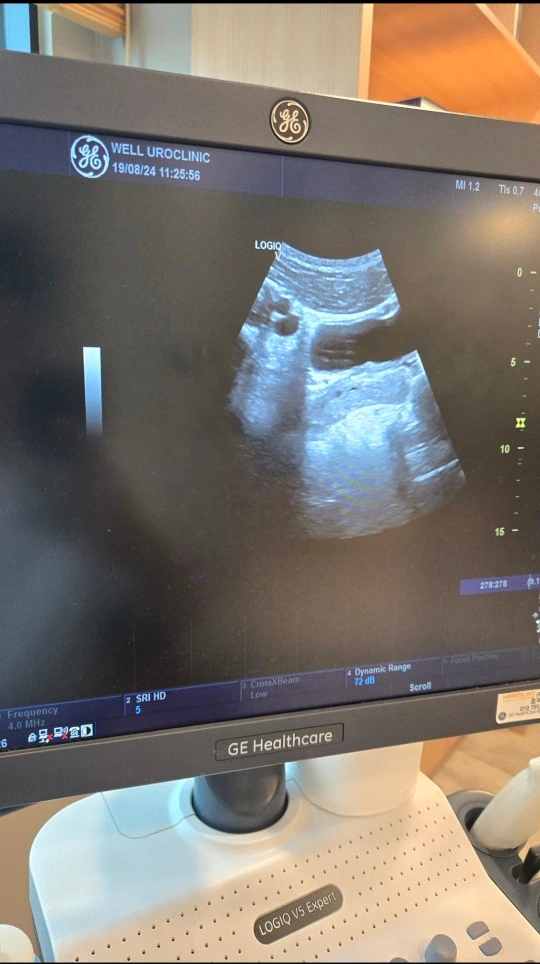

24년 8월 19일 월요일 날 비뇨기과 가서 검사해 보니 결석이 다 빠져나갔다 하셨다.

그래서 난 선생님한테 여쭤봤다."혹시 운동은 얼마큼 해야 될까요?","마라톤 뛰어도 될까요?","무리하면 안 되겠죠?" 선생님 답변은 "사람이 하던 거 안 하려면 어떻게 버티고 살아요","무리 안 할 수 있어요?"

팩트 폭행에 당황했지만 "넵 감사합니다" 하고 기쁨 마음으로 병원 나왔다.

앞으로 예전처럼 무리만 안 하면 1년에 1번씩 검사만 하러 오시라고도 했다. 몸도 점점 나아지고 아직은 안정적인 직장을 잡지 못했지만 현재 내가 인력소 통해 나가면서 돈도 벌고 무사히 집 도착해서 샤워하고 밥 먹고 운동 가고 공부하고 이렇게 할 수 있다는 상황이 그저 "너무 좋다" 이 말밖에 떠오르지 않는다.